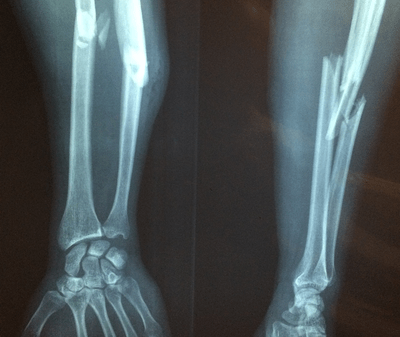

C. 骨质疏松症的症状

E. 骨质疏松症的诊断